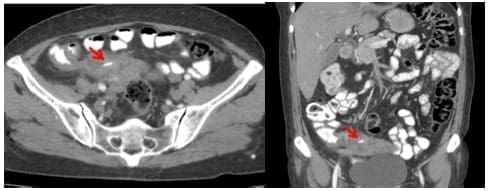

Se realizó una tomografía computarizada contrastada observando un marcado engrosamiento del apéndice cecal, perdida de su configuración y una colección heterogénea multiloculada con una imagen hiperdensa lineal de aproximadamente 18 mm en su interior, sugestiva de cuerpo extraño, hallazgos compatibles con apendicitis aguda, perforación contenida y formación de absceso periapendicular (figura 1).

Figura 1. Tomografia computarizada de abdomen con contraste, la flecha señala el cuerpo extraño